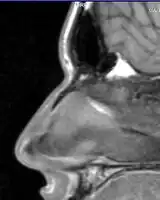

A nasal fracture, commonly referred to as a broken nose, is a fracture of one of the bones of the nose.[2] Symptoms may include bleeding, swelling, bruising, and an inability to breathe through the nose.[1][2] They may be complicated by other facial fractures or a septal hematoma.[1]

Symptoms of a broken nose include bruising, swelling, tenderness, pain, deformity, and/or bleeding of the nose and nasal region of the face. The patient may have difficulty breathing, or excessive nosebleeds (if the nasal mucosa are damaged). The patient may also have bruising around one or both eyes.

Nasal fractures are usually identified visually and through physical examination.[1] Medical imaging is generally not recommended.[1][2] A priority is to distinguish simple fractures limited to the nasal bones (Type 1) from fractures that also involve other facial bones and/or the nasal septum (Types 2 and 3). In simple Type 1 fractures X-Rays supply surprisingly little information beyond clinical examination. However, diagnosis may be confirmed with X-rays or CT scans, and these are required if other facial injuries are suspected.[2]